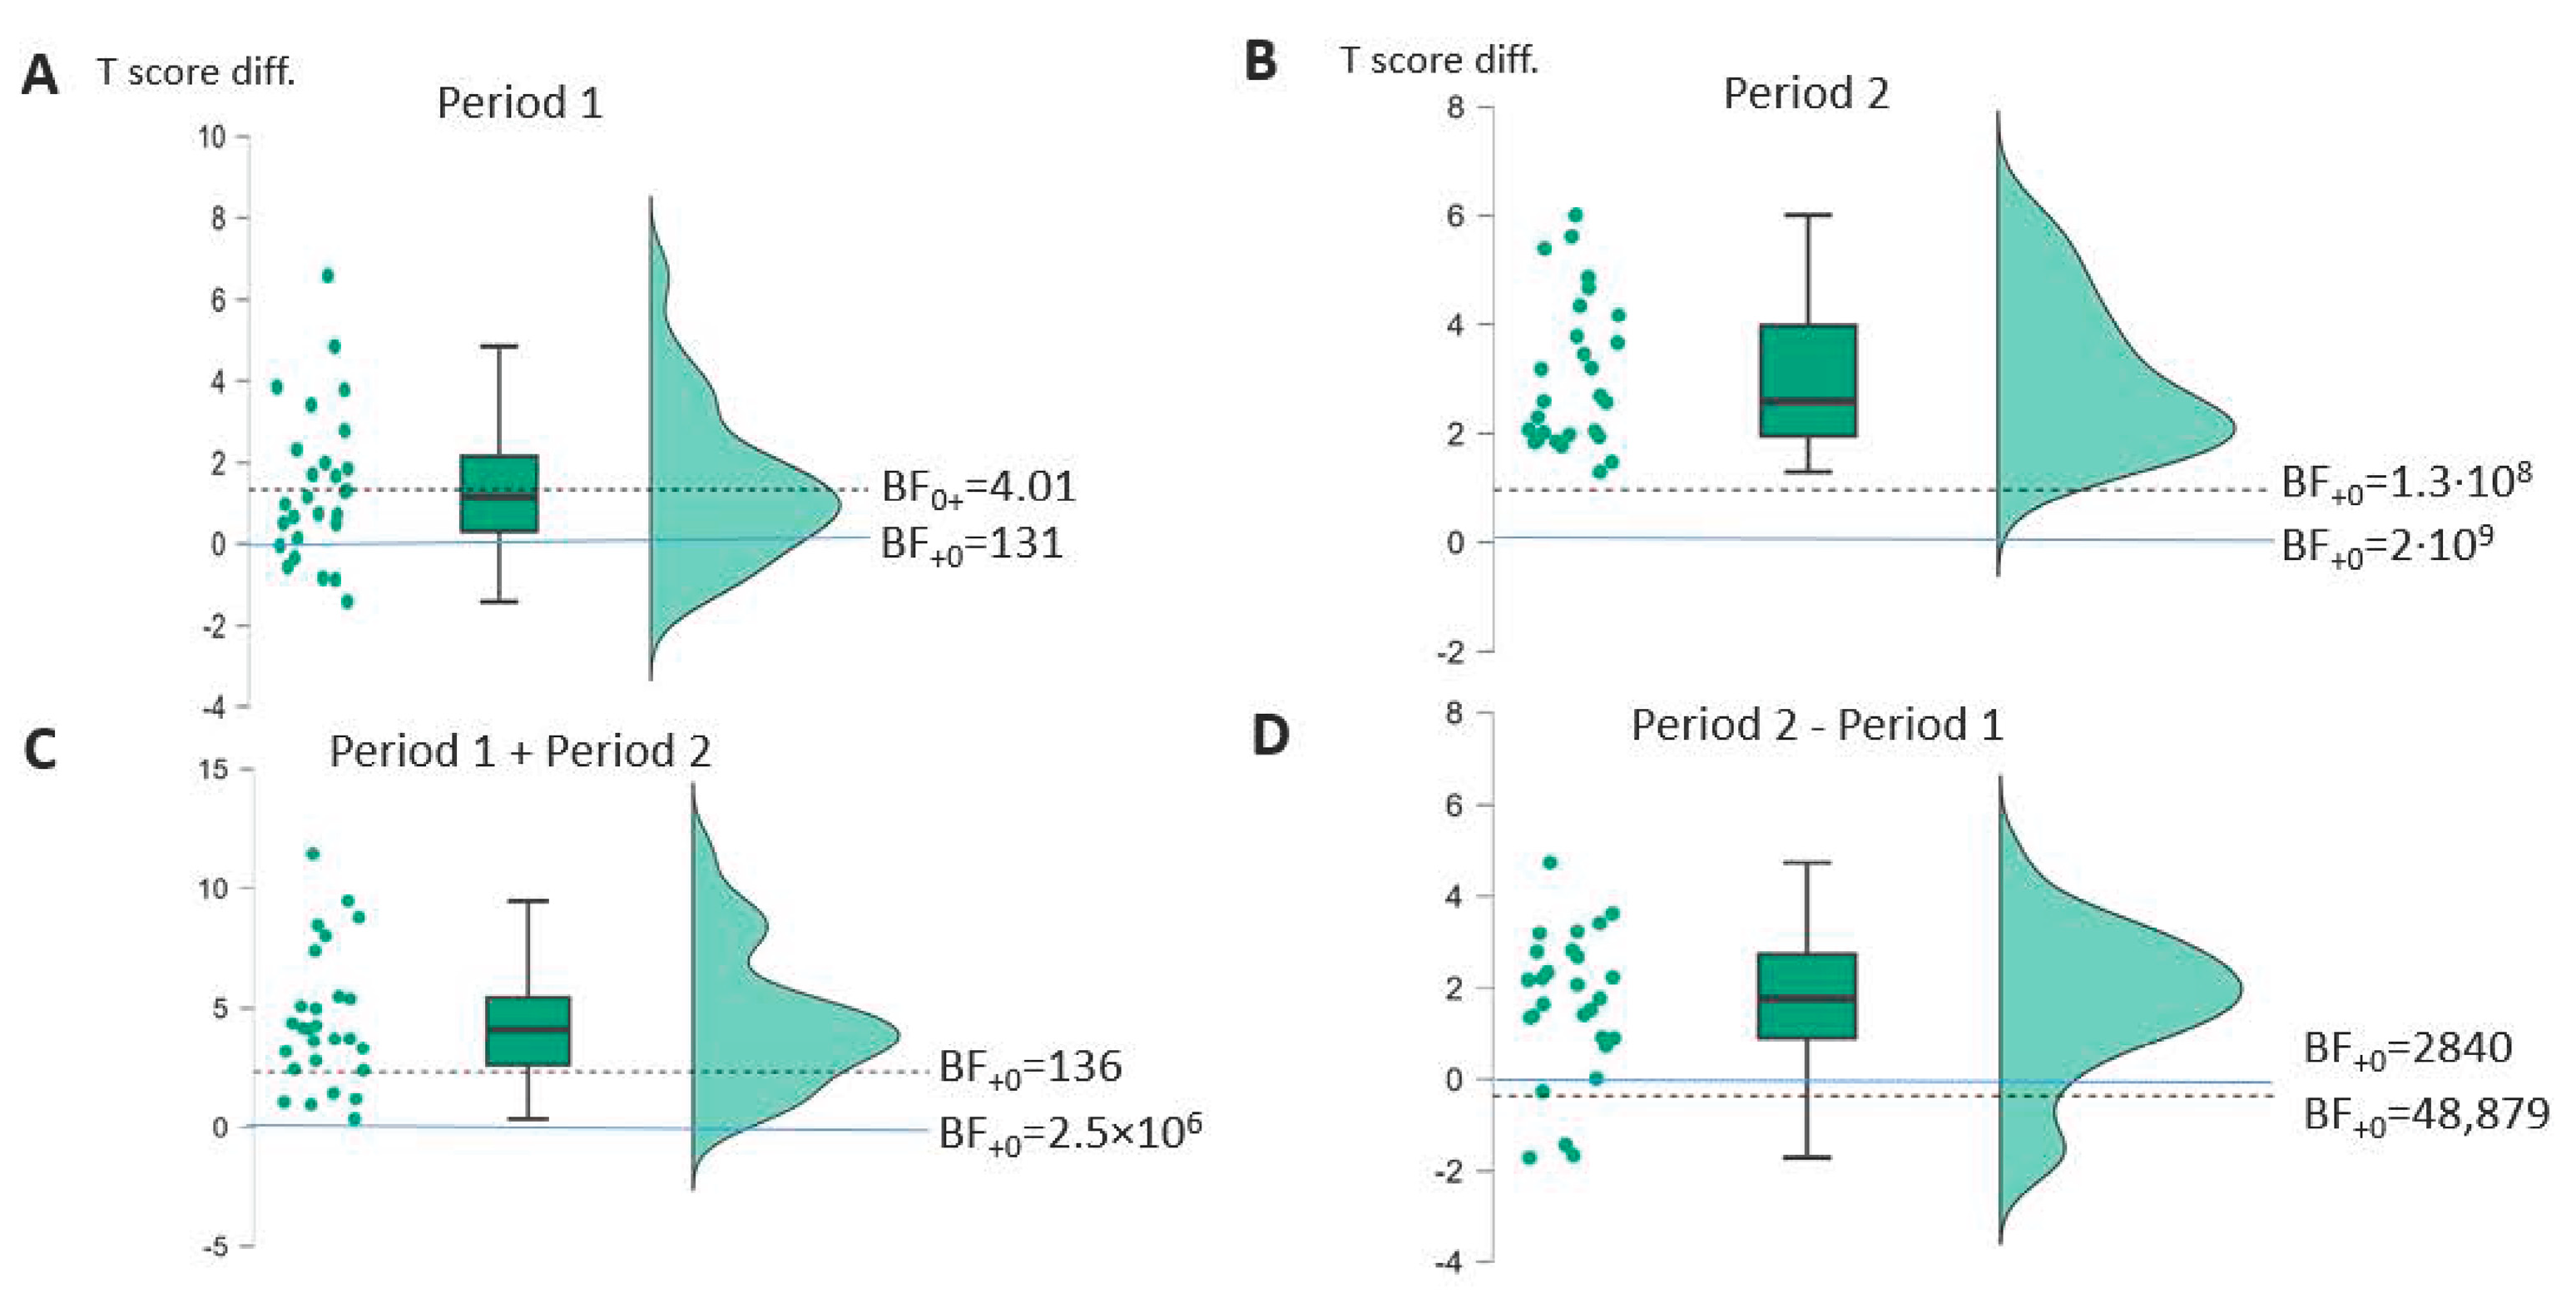

| Profile | 3.99 (<0.001) | 0.77 [0.40–] | BF+0 131 | 11.61 (<0.001) | 2.24 [1.63–] | BF+0 2 × 109 | 5.29 (<0.001) | 1.02 [0.62–] | BF+0 2840 | 8.23 (<0.001) | 1.58 [1.10–] | BF+0 2.5 × 106 |

| A | Period 1 | Period 2 | Period 2 − 1 | Period 1 + 2 | ||||||||

| AAT (n = 27) | t(26) * (p-v.) | Cohen d [95%-CI] | Bayes Factor | t(26) * (p-v.) | Cohen d [95%-CI] | Bayes Factor | t(26) * (p-v.) | Cohen d [95%-CI] | Bayes Factor | t(26) * (p-v.) | Cohen d [95%-CI] | Bayes Factor |

| Profile | 0.25 (0.40) | 0.19 [−0.27–∞] | BF0+ 4.01 | 7.94 (<0.001) | 1.53 [1.05–∞] | BF+0 1.3 × 108 | 6.49 (<0.001) | 1.25 [0.82–∞] | BF+0 48,879 | 4.01 (<0.001) | 0.77 [0.40–∞] | BF+0 136 |

| TT | 1.69 (0.052) | 0.32 [−0.01–∞] | BF0+ 1.33 | 4.63 (<0.001) | 0.89 [0.51–∞] | BF+0 585 | 1.39 (0.089) | 0.27 [−0.06–∞] | BF0+ 1.16 | 4.44 (<0.001) | 0.85 [0.48–∞] | BF+0 58 |

| REP | 0.80 (0.21) | 0.16 [−0.17–∞] | BF0+ 2.36 | 4.51 (<0.001) | 0.87 [0.49–∞] | BF+0 438 | 3.49 (<0.001) | 0.67 [0.32–∞] | BF+0 42 | 3.08 (0.002) | 0.59 [0.24–∞] | BF+0 17 |

| WRIT | 0.76 (0.23) | 0.15 [−0.17–∞] | BF0+ 2.47 | 2.83 (0.004) | 0.54 [0.20–∞] | BF+0 10.2 | 1.06 (0.15) | 0.21 [−0.12–∞] | BF0+ 1.75 | 3.19 (0.002) | 0.61 [0.26–∞] | BF+0 22 |

| NAM | 0.28 (0.39) | 0.05 [−0.26–∞] | BF0+ 3.91 | 4.17 (<0.001) | 0.80 [0.43–∞] | BF+0 196 | 2.17 (0.019) | 0.42 [0.08–∞] | BF+0 2.96 | 3.19 (0.002) | 0.62 [0.26–∞] | BF+0 7.55 |

| COMP | −0.76 (0.77) | −0.15 [−0.46–∞] | BF0+ 7.99 | 3.84 (<0.001) | 0.74 [0.37–∞] | BF+0 91 | 2.98 (0.003) | 0.57 [0.23–∞] | BF+0 14 | 3.28 (0.001) | 0.63 [0.28–∞] | BF+0 27 |